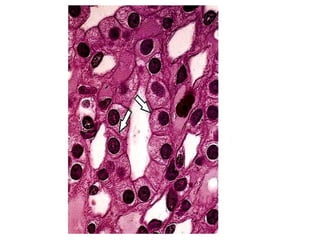

Epitelio de transição da bexiga